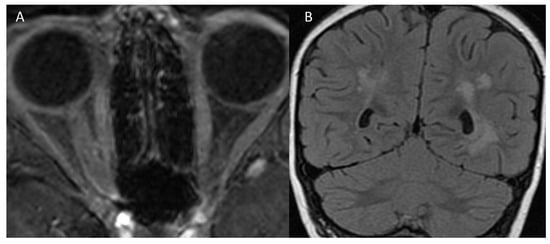

| MRI | Left optic nerve: hyperintensity (T2) Two millimetric T2 hyperintense cerebellar foci | Right optic nerve: hyperintensity (STIR), contrast enhancement ADEM outcomes | Right optic nerve: small hyperintensity (T2) Multiple juxtacortical, infratentorial, and periventricular demyelinating lesions; four lesions with contrast enhancement | Right and left optic nerves: retrobulbar bilateral swelling, contrast enhancement |